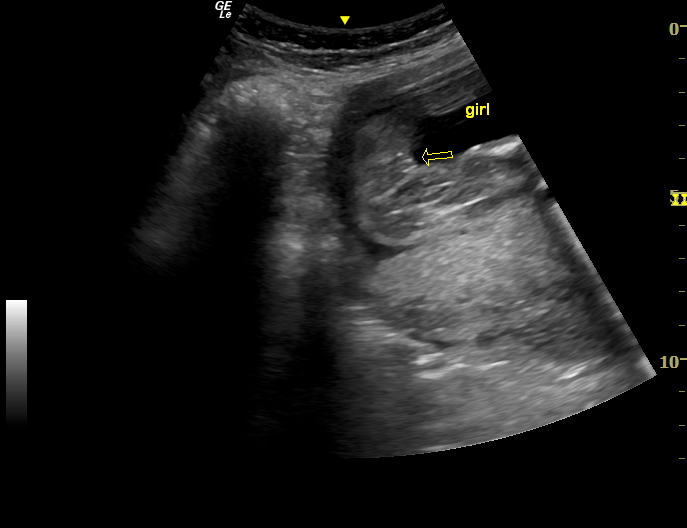

Monday I went for my 20 week ultrasound, at 20w 2d. Though I had swayed girl, I was expecting to hear boy, and did, pointing to this picture and the "good looking scrotum" in it. Well 5 minutes after this, the baby pottied (which was pretty cool to see, actually) and the tech suddenly got a bit flustered and changed his tune. "I apologize," he said, "I think that is a girl. We should have seen a clear penis pop out there when the baby went, and I don't see that. Sometimes the labia gets swollen and makes it hard to tell...I'm like 90/10...never 100%..." and I didn't hear any more and wouldn't have believed a word of it at that point anyway. I assumed he had grabbed a couple of photos for me on my usb drive after his flip flop, but discovered when I got home that he hadn't. So I have no comparison shots. Nothing clear enough either way. Now I am debating what to do. I have to have another ultrasound in 8 weeks due to a low lying placenta, but 1. I don't know if I can wait that long, and 2. I don't really want to pay for an extra ultrasound in between. On the upside, the next one should be done by my regular guy who I have seen in my last 4 pregnancies, and I tend to trust him more.